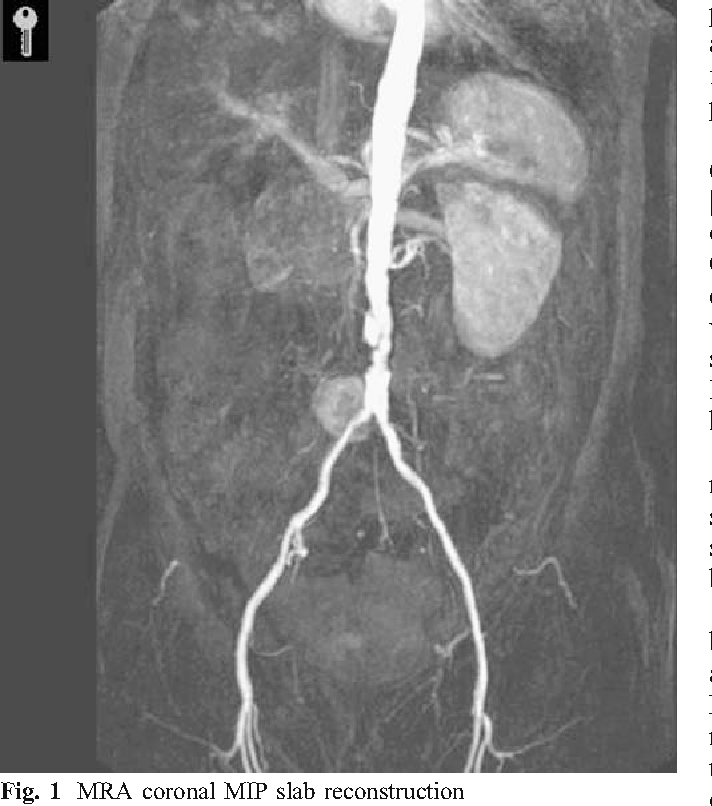

paraganglioma at the organ of zuckerkandl